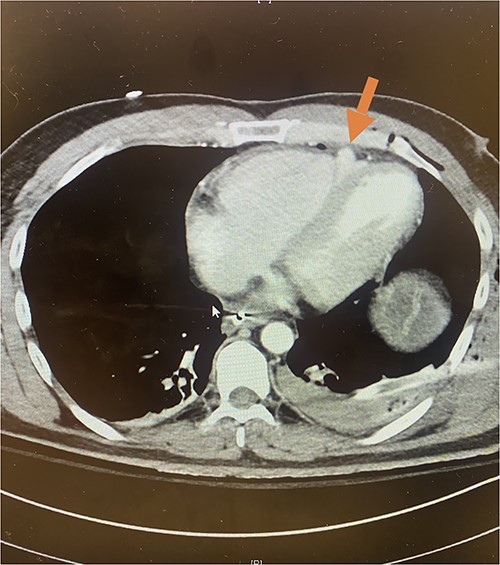

Given his hemodynamic normalization without ongoing transfusion requirements, he was taken to the computed tomography (CT) scanner for axial imaging of the head, chest, abdomen and pelvis. A CT angiogram of the chest revealed trace pneumopericardium and pneumomediastinum with trace hemopericardium. A 1.7 × 0.7 cm out-pouching at the anterior aspect of the right ventricular apex concerning for a traumatic pseudoaneurysm was also detected (see Figs 2 and 3). His other injuries were notable for subarachnoid and subdural hemorrhages, left temporal bone fracture, open mandibular fracture, left 3–6th, 10th and 11th rib fractures, a 4th lumbar vertebrae burst fracture with 1st and 3rd lumbar vertebrae compression fractures, 8–11th thoracic vertebrae compression fractures, and a left femoral neck fracture. He was subsequently transferred back to the trauma bay where a formal trans-thoracic echocardiogram was immediately performed, which demonstrated a dyskinetic area of the right ventricular apex with paradoxical out-pouching during systole—suggestive of pseudoaneurysm and confirming the diagnosis on axial imaging.

Axial CT imaging demonstrating pseudoaneurysm of right ventricular free wall rupture.